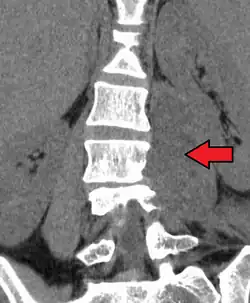

| Paraspinal abscess in the psoas muscle | |

Psoas abscess is a collection of pus (abscess) in the iliopsoas muscle compartment.[1][2][3] It can be classified into primary psoas abscess (caused by hematogenous or lymphatic spread of a pathogen) and secondary psoas abscess (resulting from contiguous spread from an adjacent infectious focus).[3]